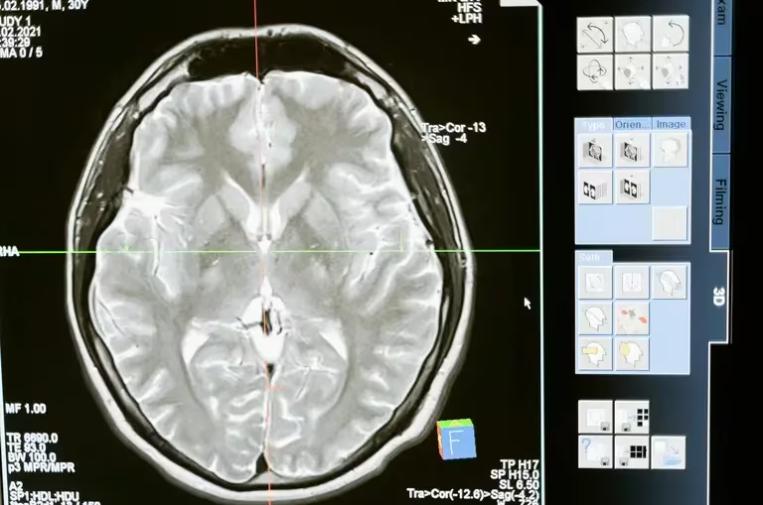

La historia de un niño de 13 años está dando la vuelta al mundo, tras vencer un cáncer considerado uno de los más letales. El pequeño de 13 años se curó de un glioma en el tronco cerebral, un tumor inoperable que suele tratarse con radioterapia para frenar su avance.

Los resultados fueron un verdadero milagro, ya que comenzó a responder de manera positiva, hasta que el tumor desapareció. “A lo largo de las IRM, vi el tumor desaparecer completamente”, relató el pediatra, quien a pesar del buen resultado, no quería que Lucas dejara el medicamento por temor a que el cáncer volviera.